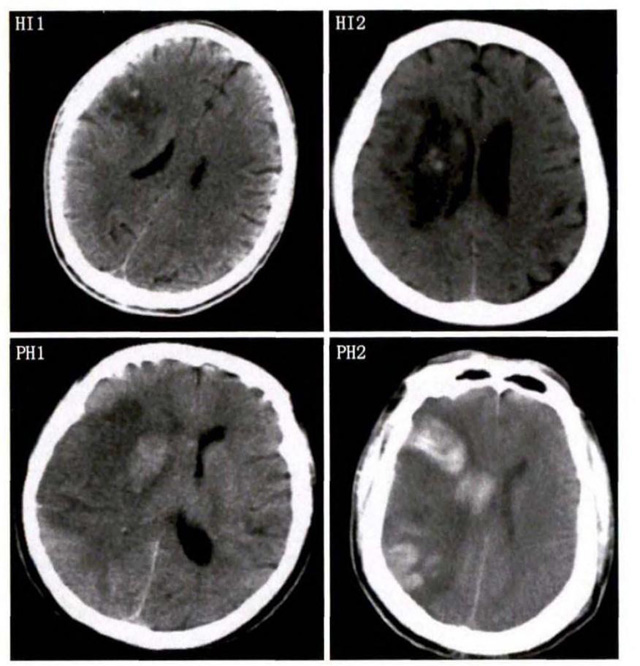

中、老年病患,有動(dòng)脈粥樣硬化及高血壓病等腦卒中的危險(xiǎn)因素,發(fā)病結(jié)合神經(jīng)系統(tǒng)癥狀和體征,應(yīng)當(dāng)考慮急性腦梗死的可能。再經(jīng)腦CT/MRI發(fā)現(xiàn)梗死灶,或排除腦出血、炎癥性疾病等,診斷即可確定。腦梗死有時(shí)頗似小量腦出血的臨床表現(xiàn)。腦栓塞在任何年齡都可以有發(fā)病的風(fēng)險(xiǎn),可以在幾秒到幾分鐘達(dá)到頂峰。會(huì)有偏癱不能說話等局部神經(jīng)功能損壞。栓子來源很種,可能是冠心病、心肌梗塞、心內(nèi)膜炎等。合并心房纖顫,結(jié)合其他臟器官的支持診斷,CT跟磁共振都可以檢查確定栓塞位置數(shù)量還有是不是有伴發(fā)出血等問題??梢詭椭\斷。

中老年有高血壓糖尿病發(fā)病病史,起病神經(jīng)功能缺損癥狀,臨床表現(xiàn)為腔隙綜合征,即可初步診斷本病。如果CT或磁共振證實(shí)有與神經(jīng)功能缺失一致的腦部腔隙病灶, 符合大腦半球或腦干深部的小穿通動(dòng)脈病變,即可明確診斷。少數(shù)患者隱匿起病,無明顯臨床癥狀,在影像學(xué)檢查時(shí)發(fā)現(xiàn)。